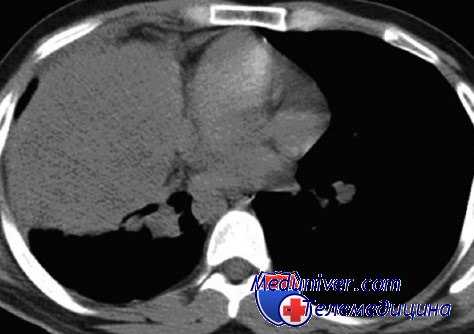

В 60 (73,1%) случаях выполнена правосторонняя пневмонэктомия (ПЭ) с ЦР трахеи и левого главного бронха (ЛГБ), в 5 (6,1%) - левосторонняя ПЭ с ЦР трахеи и правого главного бронха (ПГБ), в 12 (14,6%) - правосторонняя верхняя лобэктомия (ВЛЭ) с ЦР трахеи, ЛГБ и промежуточных бронхов, причем в 3 случаях реконструкция выполнена с формированием 2 анастомозов, а в 9 - по типу «штаны" (рис. 1 ). В 3 случаях выполнена изолированная резекция карины с ее реконструкцией в

- верхней лоб(билоб)эктомии и резекции карины трахеи при перибронхиально-узловатом росте рака верхнедолевого бронха с переходом на боковую стенку главного до его проксимальной части и/или трахеобронхиального угла (рис. 2 );